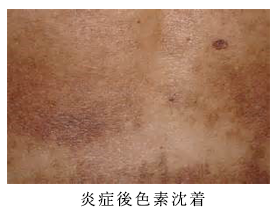

炎症後色素沈着の治療を皮膚科専門医が症例写真で解説うらた皮膚科。

☆背中の色素沈着治療~症例写真セイコメディカルビューティクリニック鹿児島福岡。

炎症後色素沈着新潟市の皮膚科 RIKA皮膚科・形成外科クリニック新潟市女池上山。

肝斑、炎症後色素沈着治療の症例写真横浜・桜木町の テティス横濱美容皮膚科。

炎症後色素沈着を治すには?シミやニキビ跡と何が違うの?美容皮膚科の町田マリアクリニック。

炎症後色素沈着とは前田メディカルクリニック栃木県小山市の美容皮膚科。